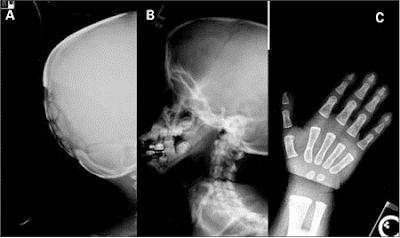

Menyusul evaluasi segmen anggota gerak dan plat pertumbuhan epifiseal, fokus pada keseluruhan struktur skeletal yang tersedia dalam survei skeletal genetik mensyaratkan wajib mengenal satu displasia skeletal yang terjelaskan dengan baik dari satu yang sebelumnya berkategori kasar menjadi sebuah kelompok spesifik. Evaluasi yang akurat ini akan meliputi satu penelusuran berbagai temuan patognomonik, seperti misalnya tulang berbentuk siput dari displasia Schneckenbecken (Gambar 9), tampilan “berrenda (lacy)” dari krista iliaka pada sindrom Dygve-Melchior_Clausen (Gambar 10), dan hilangnya angulus mandibula disertai dengan wormian bone dan acroosteolysis pada pycnodysostosis (Gambar 11 a, b, c) (7).

Gambar 11

a,b,c. Pycnodysostosis. Hilangnya angulus mandibula dengan wormian bones, fontanela besar dan acroosteolysis pada distal falang tangan